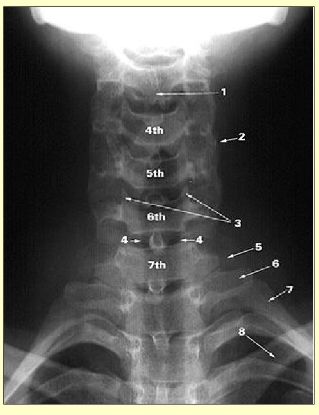

Label this image

bifid spinous process of C3

superimposed articular processes

uncinate process

trachea

transverse process of C7

transverse process of T1

1st rib

clavicle